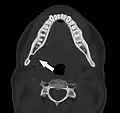

Additional images

Stafne bone cavity seen on axial CT